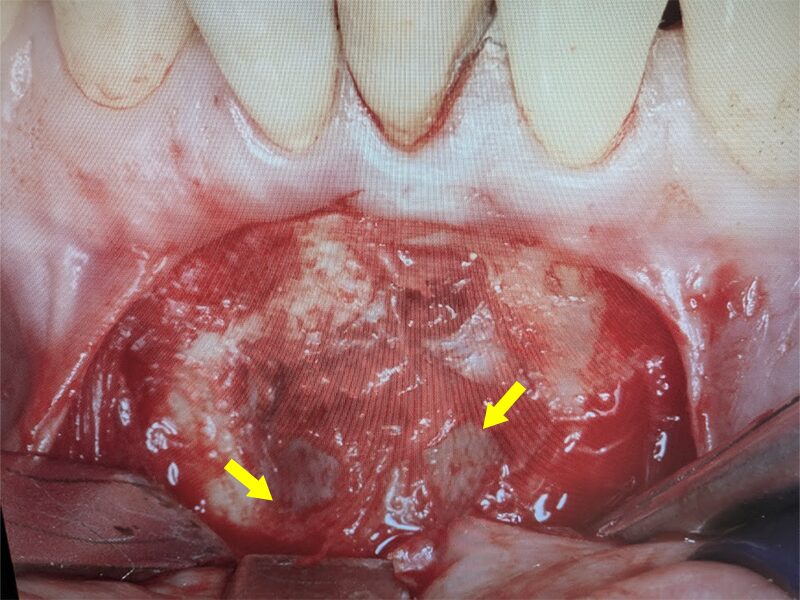

骨内の嚢胞にアプローチします。ガーゼで鈍的に剥離します。

骨内と嚢胞が分離してきています。上方に病巣の原因である歯根の先端が確認されました。

嚢胞壁を壊さないように骨から分離を行います。